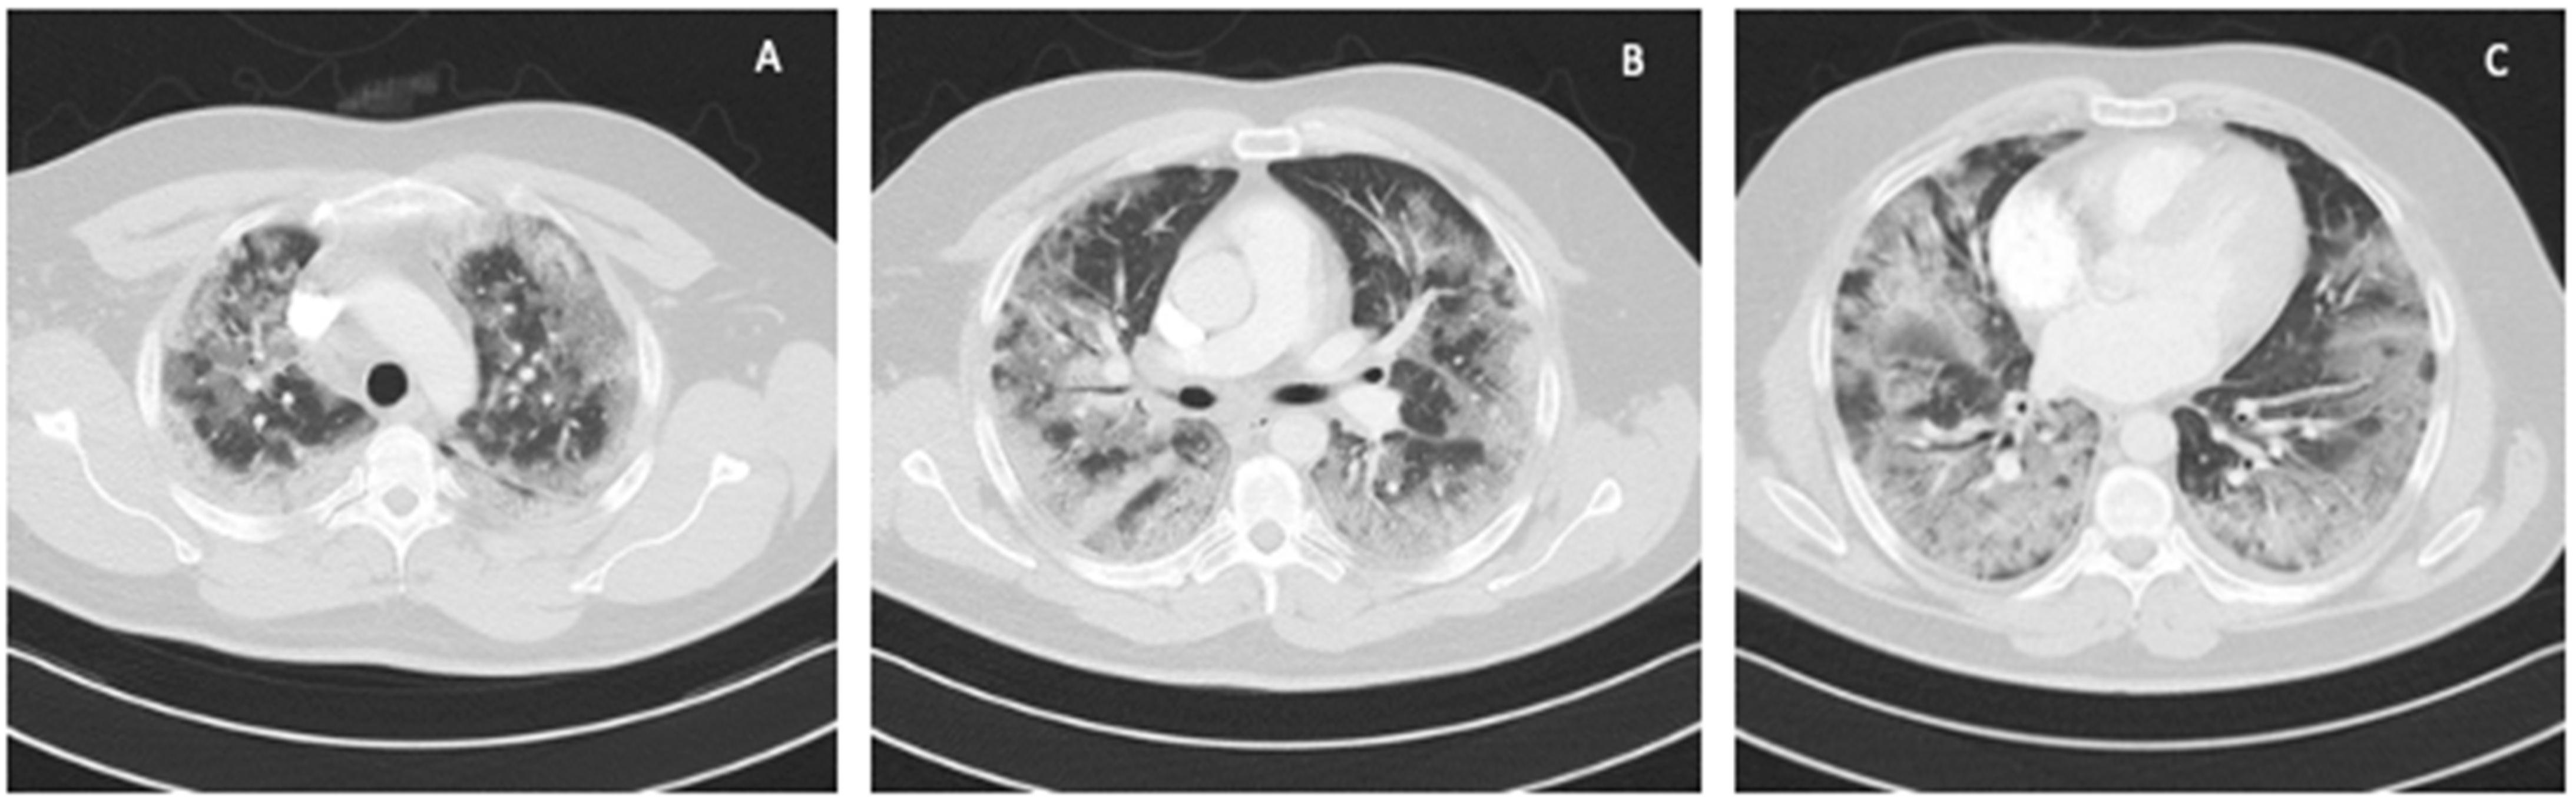

The ICU team used NIV through an oronasal mask in PS/CPAP mode with FiO2 of 1.0. Due to the increasing symptoms of respiratory failure (PaO2 = 61 mmHg, PaCO2 = 66.6 mmHg), dyspnea, and tachypnoea >40 BPM, as well as significant respiratory effort and disturbances of consciousness, the patient was intubated, and 4 h after admission to the ICU, mechanical ventilation was initiated in the SIMV (PC) mode with FiO2 of 0.9, PEEP = 13 cmH2O, Pins = 24 cmH2O, Cdyn = 46 mL/cmH2O, Pplat = 21 cmH2O, obtaining optimal MV [14]. Deep hypoxemia with a PaO2/FiO2 ratio <60 was observed. An infectious disease specialist did not qualify the patient for treatment with remdesivir. Multimodal deep analgosedation was included. Dexamethasone IV at a dose of 6 mg, as per NIH guidelines, and therapeutic doses of low-molecular-weight heparin were used [12]. LUS imaging showed a bilateral B-profile and massive basal consolidations. The cardiac ultrasound demonstrated the proper function of the right and left ventricles, and no valvular changes were recorded. On day 2 from the initiation of the mechanical ventilation, the prone position maneuver was attempted; however, it was unsuccessful due to the difficulties related to the patient’s abdominal obesity. Additionally, numerous recruitment maneuvers were used, consisting of inspiration extended to 20 s with Pplat up to 30 cmH2O, performed twice, without improvement in oxygenation or increase in Cdyn. On day 4 of the ICU stay, due to PaO2/FiO2 ratio <60, a decision was made to use VV ECMO. The calculated RESP score was 4, with a class II risk and an estimated ECMO survival probability of 76%. Before cannulation, the patient underwent percutaneous Griggs tracheostomy. The implantation technique and cannulation equipment used were identical to those described in Case 1. The correct position of the cannulas was confirmed by ultrasound examination and chest X-ray (Figure 4).

Figure 4. Chest X-ray: (A) after admission to the ICU; (B) 2 days after starting VV ECMO treatment (Case 2).